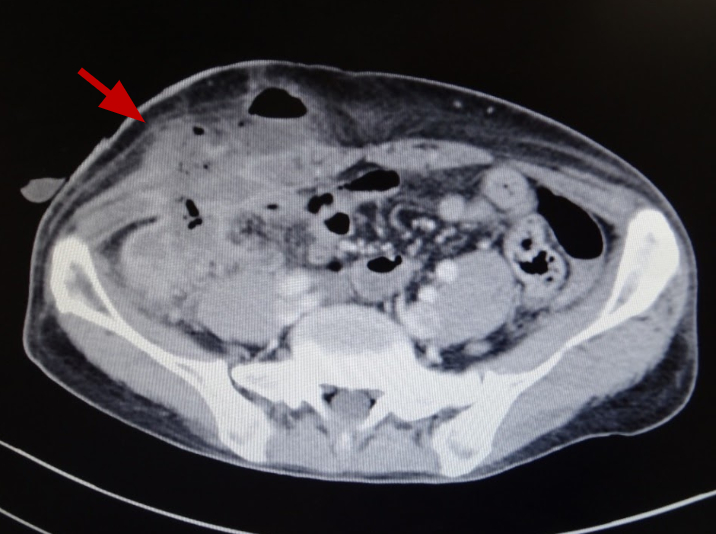

La apendicitis aguda amebiana es una manifestación infrecuente de la amebiasis y se asocia a una tasa más elevada de complicaciones y de mortalidad que la apendicitis no amebiana. La exploración histopatológica y las precauciones adicionales están justificadas cuando se sospecha de apendicitis amebiana.[9][Figure caption and citation for the preceding image starts]: Apendicitis amebiana con fístula cutánea dos semanas después de la apendicectomía (tomografía computarizada mejorada).Foto original del National Center for Global Health and Medicine, Tokio, Japón. [Citation ends].